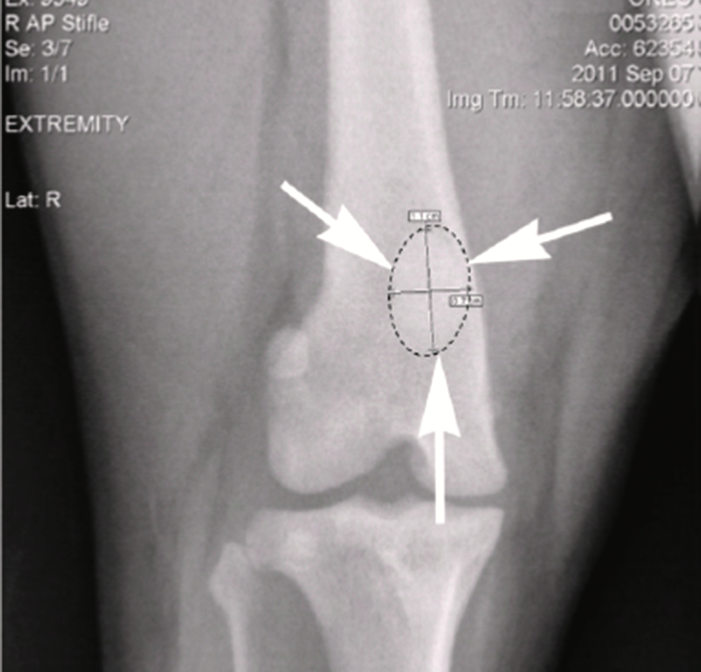

To help Oreo, OIC obtained a donated patella that was used to generate a scaled digitized copy. A biomedical engineer then converted the file into a computer-aided design (CAD) model. X-ray radiographs of Oreo’s other patella were then used to modify the CAD design to match his femur.